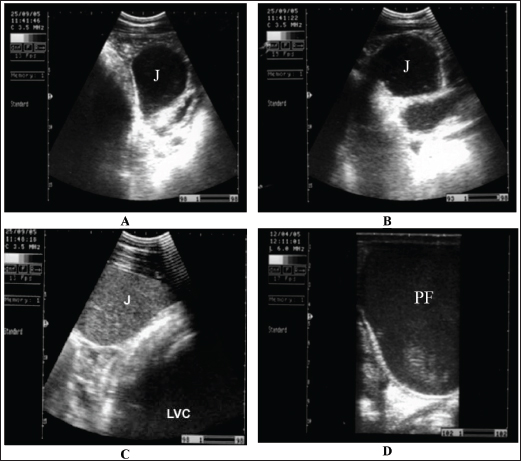

Fig. 9. Sonogram of horses with obstructive colic: (A) jejunum (J) imaged in the left ventral abdomen using a 3.5-MHz transducer. The greatly distended loop of the jejunum and its contents are of mixed echogenicity. (B) Image of jejunum in left ventral abdomen using a 3.5-MHz transducer. The greatly distended loop of the jejunum and its contents are of mixed echogenicity. (C) The jejunum and left ventral colon are obtained from the left flank region caudal to the costal arch. The jejunal contents were more echogenic. The left ventral colon shows no sacculations. (D) Pelvic flexure (PF) obtained from the transrectal window using a 6-MHz transducer. It appears that complete ileus was observed during real-time scanning.

There are many causes of obstructive and strangulation colic. It may include obstruction by fecalith or enterolith, small colon impaction, atresia coli, retention of meconium, volvulus, strangulation by pedunculated lipoma, intussusception, and herniation through mesenteric rents (Abutarbush, 2006). Abdominal distension is usually mild initially, but it progresses as the disease intensity increases (Fig. 7). Non-strangulating lesions appear as mild to moderate colicky pain that may last without a difference of intensity for up to 36 hours (Fig. 8). Ultrasound can be helpful in recognizing the compromised intestine, allowing earlier verification. Elevated gut wall thickness reflects the stages of edema and hemorrhage and may predict prognosis (Fig. 9) (Tharwat et al., 2008). In horses with obstructive colic, the small intestine, especially the jejunum, appears distended with fluid-containing ingesta, which exhibits mixed echogenicity. The peristaltic activity of healthy equines (Giusto et al., 2024). The descending colon is distended with fluid and ingesta, and the left ventral colon appears without sacculations and detectable motility. Transrectal ultrasonographic examination showed that the pelvic flexure with gas, fluid, and ingesta with no detectable contractions (Tharwat et al., 2008). In advanced cases, intestinal perforation may occur because of either severe impaction or intestinal strangulation (Fig. 10) (Tharwat et al., 2008).